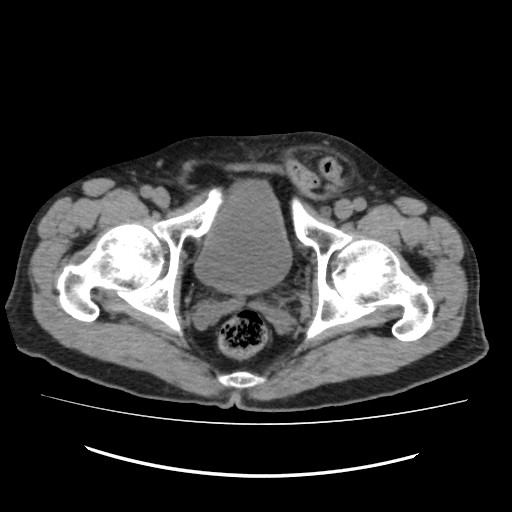

【コンピュータ断層診断装置(Computed Tomography:CT)】高性能16列マルチスライスCTで精密検査が受けられます。

短時間で断層像(輪切り)が鮮明に撮れます。

コンピュータ断層診断装置(Computed Tomography:CT)での撮影画像例。